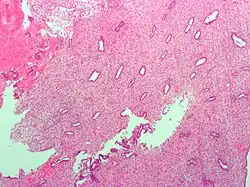

Micrograph showing endometrial stromal condensation, a finding seen in menses.

Micrograph showing endometrial stromal condensation, a finding seen in menses.